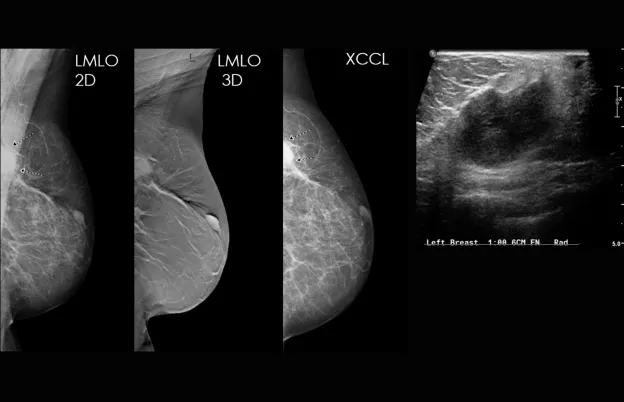

Correlate mammography and ultrasound examinations to identify suspicious areas in both imaging methods

Review case studies for correlation